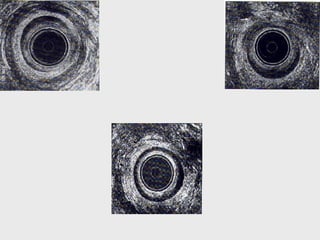

A: tessuto subepiteliale

B : sfintere anale interno

C: muscolo longitudinale

D : sfintere esterno

Scansione

superficiale F